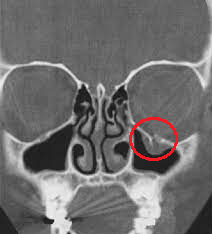

Nomeie os ossos apontados